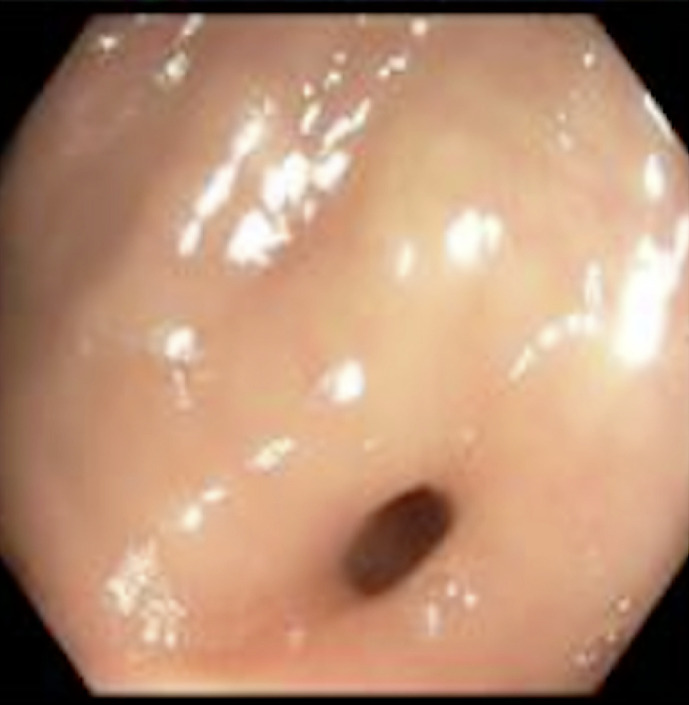

Case presentation: Our patient, a 77-year-old male, underwent an uncomplicated screening colonoscopy and was discharged home after briefly being monitored without any complaints. Later that day, the patient presented to the emergency department complaining of acute generalized abdominal pain. On presentation, the patient was found to be hypertensive and febrile with a distended abdomen with right lower quadrant tenderness on examination. Laboratory investigations noted an elevated white blood cell count with no evidence of acute appendicitis or focal inflammatory changes on contrast-enhanced abdominal and pelvic computer tomography. The patient was subsequently admitted and developed worsening right lower quadrant abdominal pain and distention overnight. Due to this worsening clinical condition, the decision was made to proceed with a diagnostic laparoscopy. After frank pus was found laparoscopically around the cecum and appendix, it was then converted to an exploratory laparotomy. Subsequently, a perforated gangrenous appendix was found with an erythematous and indurated cecum.

Abstract Image